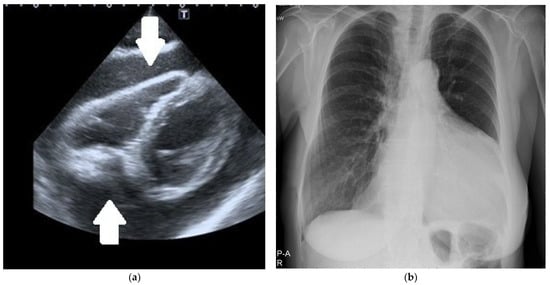

In urgent situations, a single view (usually the subcostal one) was enough to diagnose significant pericardial effusion (Figure 1a).

Figure 1. (a) Two-dimensional echocardiography. The subcostal intermediate off-axis view shows significant circumferential pericardial effusion (arrows). (b) Chest X-ray. Significant heart silhouette enlargement due to a large pericardial effusion.

Chest X-ray was performed in all the patients: an enlarged cardiac silhouette was shown in all of them (Figure 1b). Other methods of radiologic LPE visualization were applied mostly in patients who did not require immediate pericardial fluid drainage. Chest computed tomography (CT) was performed in 35 patients and chest magnetic resonance imaging (MRI) in 3.